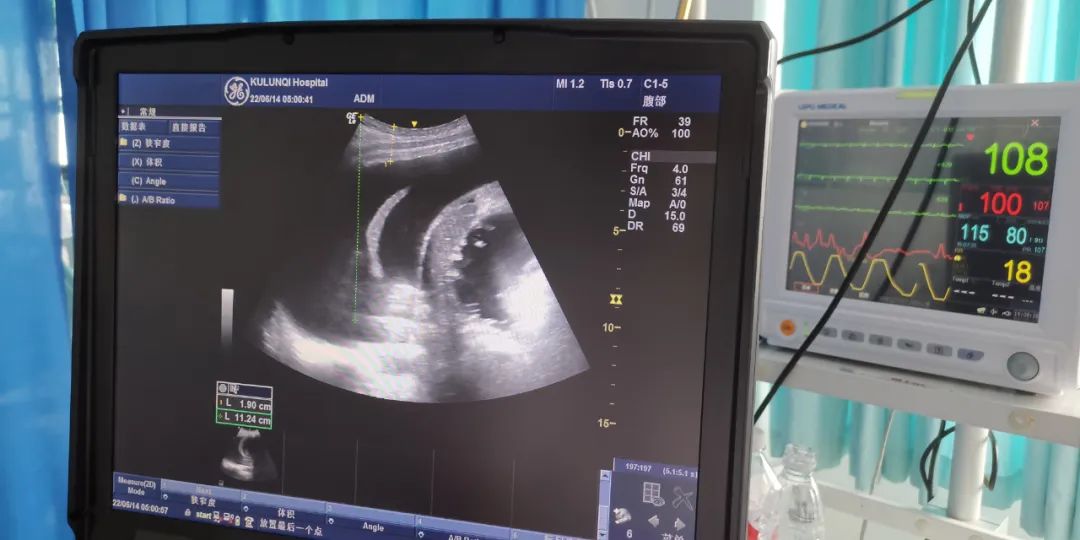

6月11日凌晨,曹新林主任负责帮扶的库伦旗人民医院ICU收治一位从外院转回准备放弃治疗的患者。该患者为34岁男性,因糖尿病,高热不退,神志不清转外院治疗,在外院行心肺复苏等抢救,病情加重,医生向家属4次交待病危,在救治无望情况下回库伦,家属已准备好了后事。入科时患者处于深昏迷状态,呼吸40次/分,血压药用两种升压药才能维持,考虑患者还比较年轻,曹新林主任本着绝不能轻易放弃的想法全力进行了呼吸机治疗,彩超定位胸穿及维持液体平衡等抢救措施,经过全科半个月的精心救治下,患者脱离生命危险,又重新站立起来了!现在已转至普通病房。